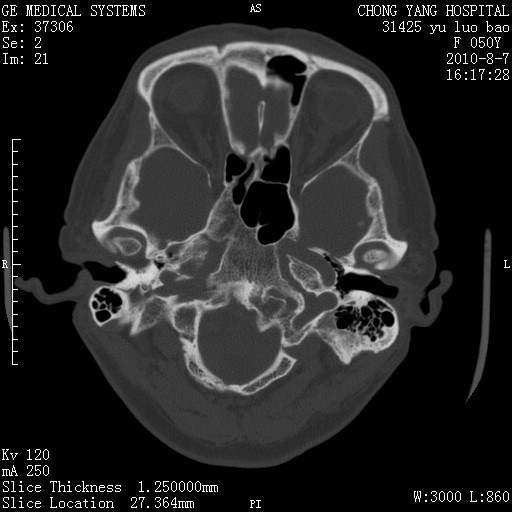

标题: CT28285:听力下降一年,头昏。 [打印本页]

标题: CT28285:听力下降一年,头昏。

右侧桥小脑角去等密度占位,右侧内听道扩大、骨质吸收,考虑:右侧听神经瘤,建议增强检查。

右侧内听道扩大、骨质吸收,中脑受压左移,考虑:右侧听神经瘤,建议增强检查。支持!

骨窗示右侧内听道扩大,考虑右侧听神经瘤。

右侧桥小脑角区等密度占位,内耳道扩大,听神经瘤